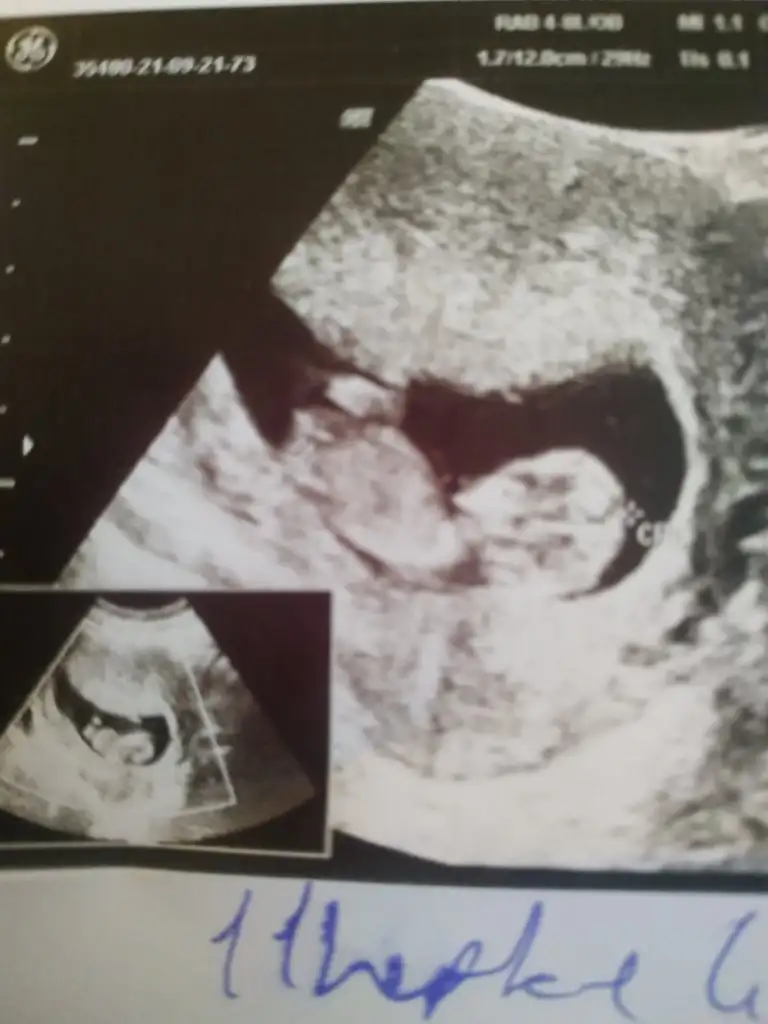

Bir de bacak arası fotosu var

• Ekran Alıntısı.webp

Ekran Alıntısı.webp

8,8 KB · Görüntüleme: 158